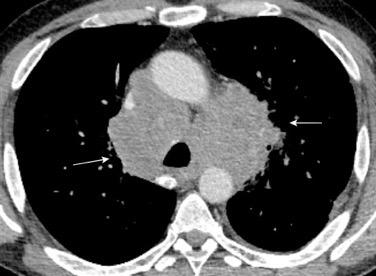

Triada de Garland

Ganglios paratraqueales derechos e hiliares bilaterales

95% de pacientes tienen ganglios hiliares bilaterales aislados o con afectación mediastínica (espec. paratraqueal derecho).

Criado E et al. Pulmonary sarcoidosis: typical and atypical manifestations at high-resolution CT with pathologic correlation. Radiographics. 2010